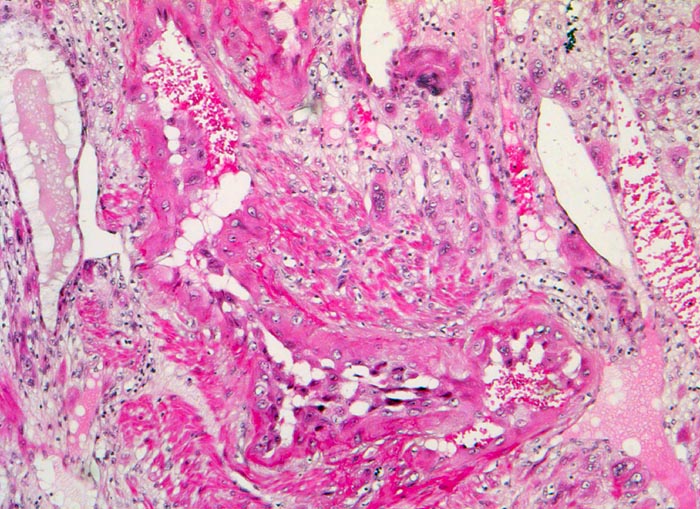

Morphologie:

• Plazenta accreta: Plazentarzotten haften dem Myometrium an ohne deziduale Zwischenschicht. Fibrin und Trophoblast kann vorhanden sein.

• Plazenta increta: Plazentaimplantation innerhalb des Myometriums.

• Plazenta percreta: Penetration der Plazentarzotten durch die gesamte Dicke des Myometriums hindurch.